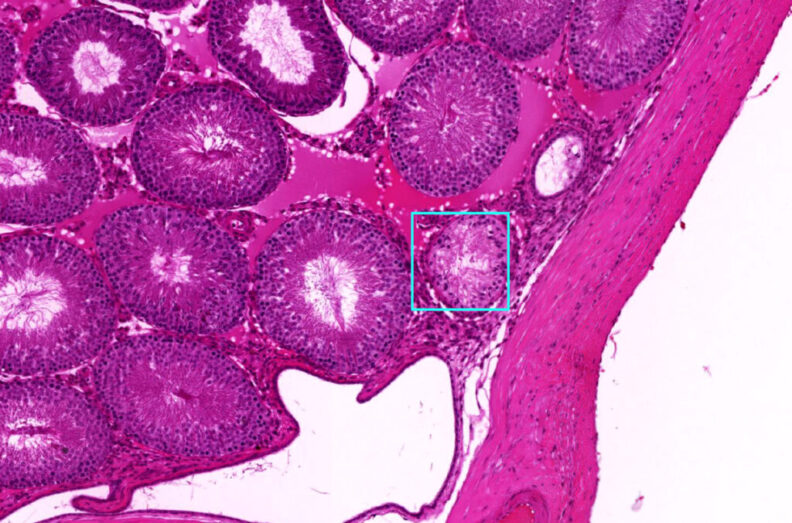

To develop the AI model, computer scientists Colin Greeley, a former WSU graduate student, and his advising professor Lawrence Holder trained it using images from past epigenetic studies conducted by Skinner’s laboratory. These studies involved molecular-level signs of disease in kidney, testes, ovarian and prostate tissues from rats and mice. The researchers then tested the AI with images from other studies, including studies identifying breast cancer and lymph node metastasis.

The research team designed the WSU deep learning model to handle extremely high-resolution, gigapixel images, meaning they contain billions of pixels. To deal with the large file sizes of these images, which can slow down even the best computer, the researchers designed the AI model to look at smaller, individual tiles but still place them in context of larger sections but in lower resolution, a process that acts sort of like zooming in and out on a microscope.